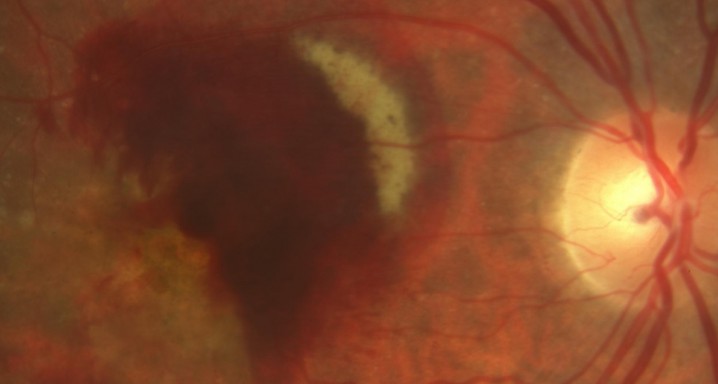

FUSION regimen: ranibizumab in treatment-naïve patients with exudative age-related macular degeneration and high visual acuity. 26/03/2013

To investigate the safety and efficacy of a combined fixed-interval and pro re nata regimen of ranibizumab (FUSION regimen) for treatment of exudative age-related macular degeneration in patients with good visual acuity at baseline. To establish whether similar efficacy to monthly regimens can be achieved with fewer injections, even in patients with good visual acuity.

This was a prospective, open-label, consecutive interventional case series in treatment-naïve patients with exudative age-related macular degeneration. The FUSION regimen consists of three phases: 1) a loading phase of two or three injections, depending on presence or absence of choroidal neovascularization activity at first follow-up, 2) administration of one injection on disappearance of exudation, and 3) subsequent administration of two separate injections at intervals 2 months apart, and then an injection every 3 months. Endpoints included visual acuity, presence of fluid, adverse events and number of injections administered.

Seventeen eyes of 17 Caucasian patients were included. Mean patient age was 76 years, and 15 patients were female. Mean baseline visual acuity was 67.5 letters (median 67), with Snellen equivalent 20/50++, ranged between 45 (20/125) and 83 (20/20--). At 3 months, mean change in best-corrected visual acuity (BCVA) was +2.3 letters (median +9) compared with baseline (p = 0.3). At 6 months, mean change in BCVA was +4.2 letters (median +9) compared with baseline (p = 0.02). At 12 months, one patient had discontinued the study. Mean change in BCVA was 5.6 (median +10) compared with baseline (p = 0.04). No patient lost ≥15 letters, and 14 patients (87.5%) lost

The FUSION regimen for ranibizumab has the potential to maintain visual gains achieved during the loading phase, as reported in studies with monthly injections, even in eyes with a relatively good visual acuity at baseline. These 12-month results warrant validation in a larger, randomized controlled trial.